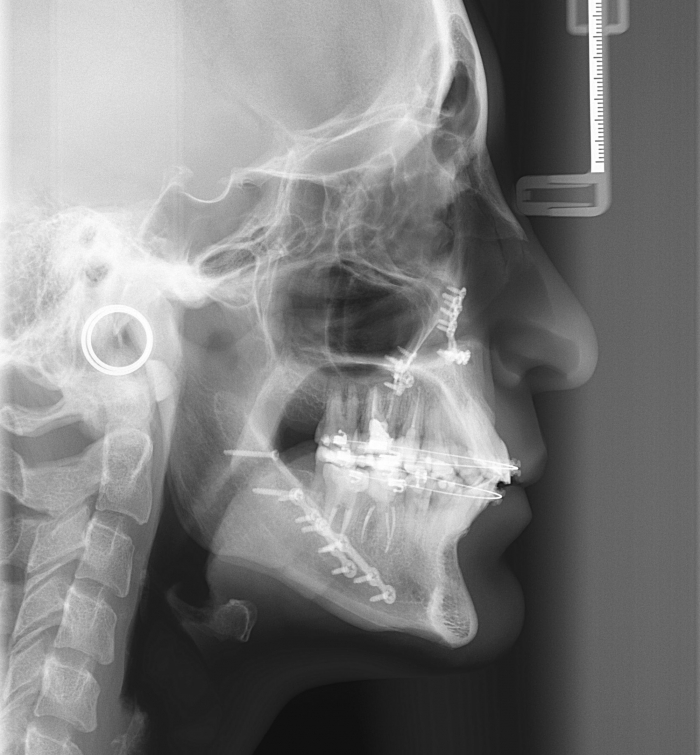

Telerradiografia inicial

Telerradiografia após a cirurgia